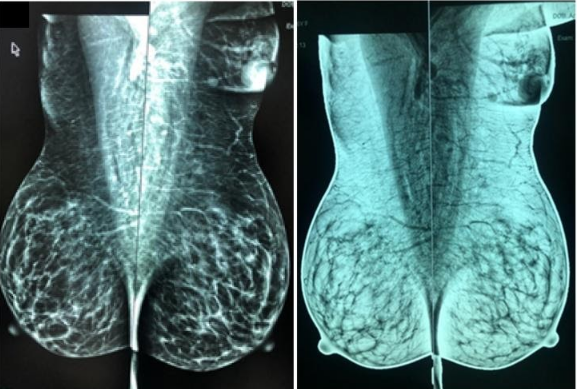

5. Đặc điểm hình ảnh và phương tiện khảo sát

Hầu hết tuyến vú được tìm thấy ngẫu nhiên trên chụp nhũ ảnh thường quy. Hình ảnh siêu âm cho thấy mô vú, không thể phân biệt với mô vú thông thường. Đôi khi, chụp cộng hưởng từ tuyến vú được thực hiện trong các trường hợp không điển hình. Biểu hiện bằng các đặc tính tín hiệu và ngấm thuốc tương tự như mô tuyến bình thường.